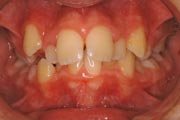

Crowding

Before